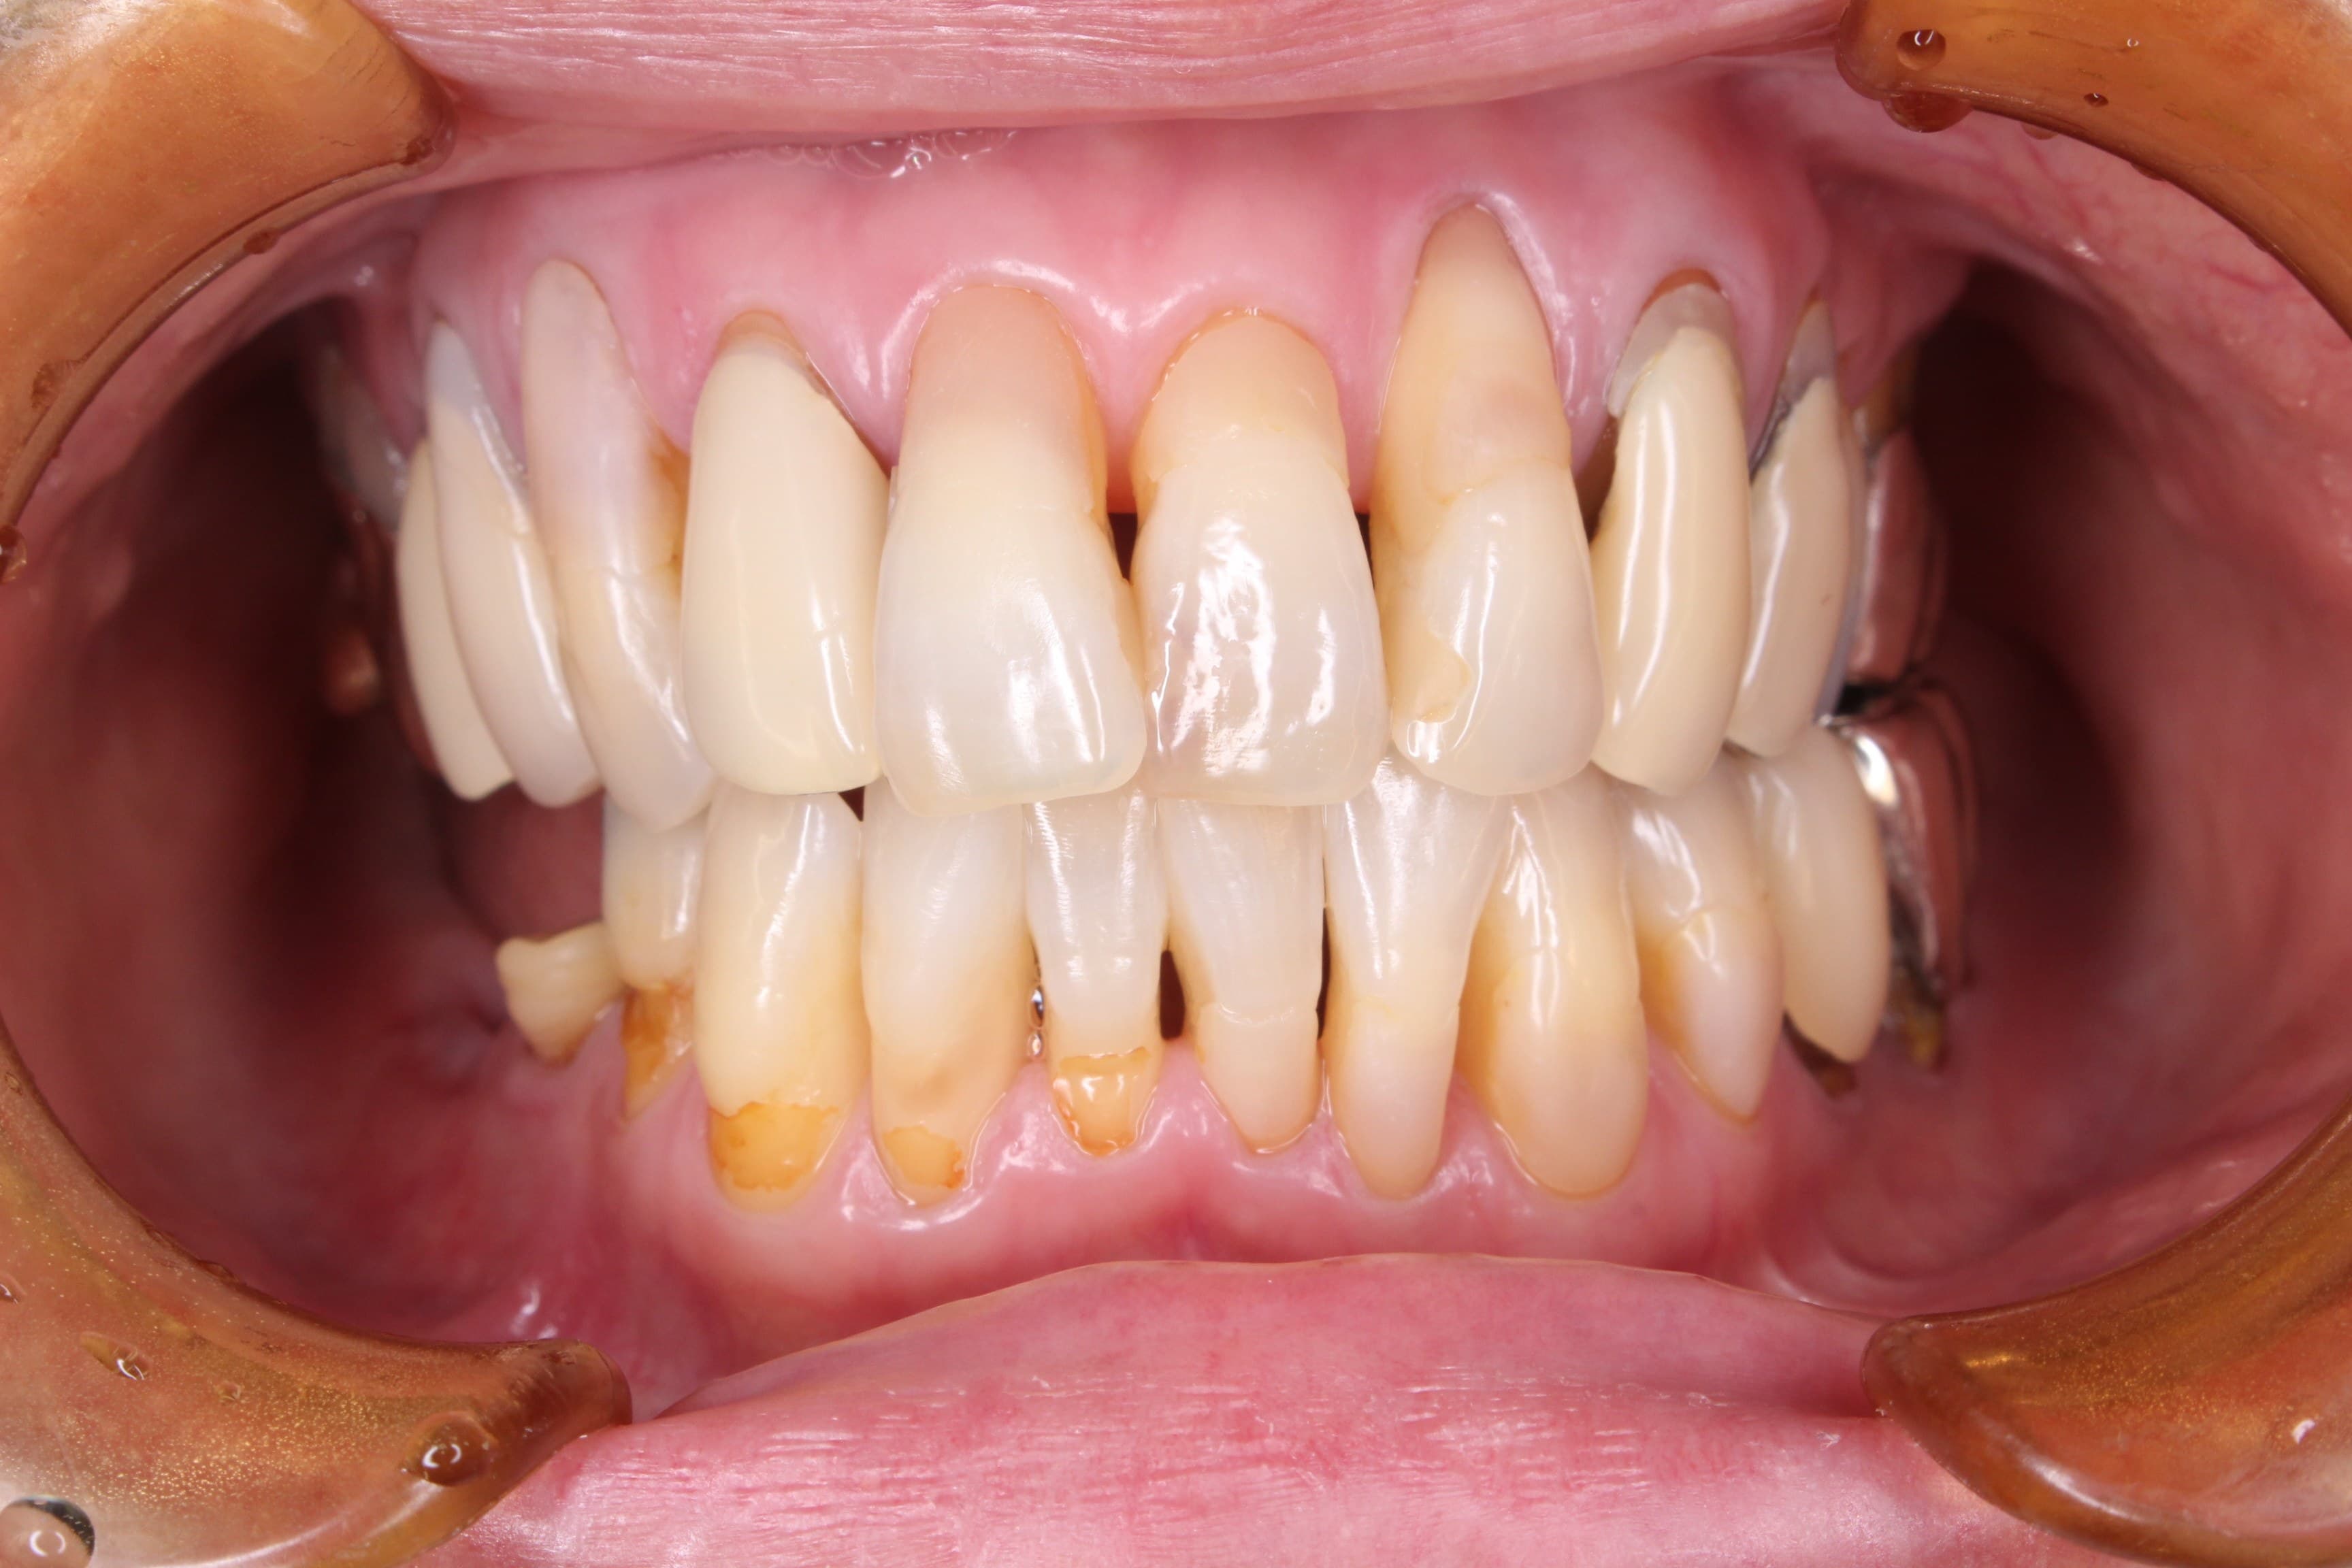

今回ご紹介するのは、長年虫歯の治療で苦労されてきた50代女性の方です。

(歯周専門治療が終了してこれから院長と虫歯の治療を行く予定です)

歯磨きはかなり気を付けて欠かさず歯間ブラシも使っている。歯磨き粉もフッ素入り。定期健診で悪い所があれば、直ぐに治療をしてきた。

なのに、

虫歯の治療が次から次へと必要になる。

この方もそんな一人でした。